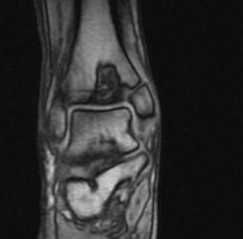

![]() |